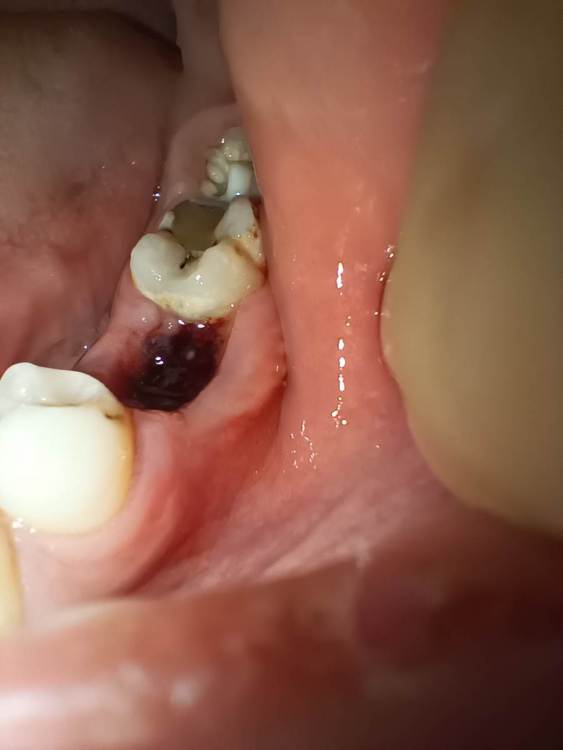

Scaurusss Опубликовано 19 ноября, 2022 Поделиться Опубликовано 19 ноября, 2022 После удаления зуба сказали 2 часа не есть, не полоскать. Спустя 2 часа прополоскал рот и оттуда вышел сгусток, и только сейчас узнал, что так нельзя было делать. У меня вопрос, сохранился или восстановился ли он у меня? Фото прикреплено. Если же нет, то что мне делать? Ссылка на комментарий

Scaurusss Опубликовано 19 ноября, 2022 Автор Поделиться Опубликовано 19 ноября, 2022 @Irouil вчера в 18 часов (прополоскал в 20:15) фото сделано сегодня в 9 часов утра Ссылка на комментарий

Scaurusss Опубликовано 19 ноября, 2022 Автор Поделиться Опубликовано 19 ноября, 2022 @IvanK Спасибо, т.е сгусток сохранился и просто следовать указаниям? Ссылка на комментарий

Irouil Опубликовано 19 ноября, 2022 Поделиться Опубликовано 19 ноября, 2022 8 часов назад, Scaurusss сказал: @Irouil вчера в 18 часов (прополоскал в 20:15) фото сделано сегодня в 9 часов утра Пока все выглядит нормально 1 Ссылка на комментарий